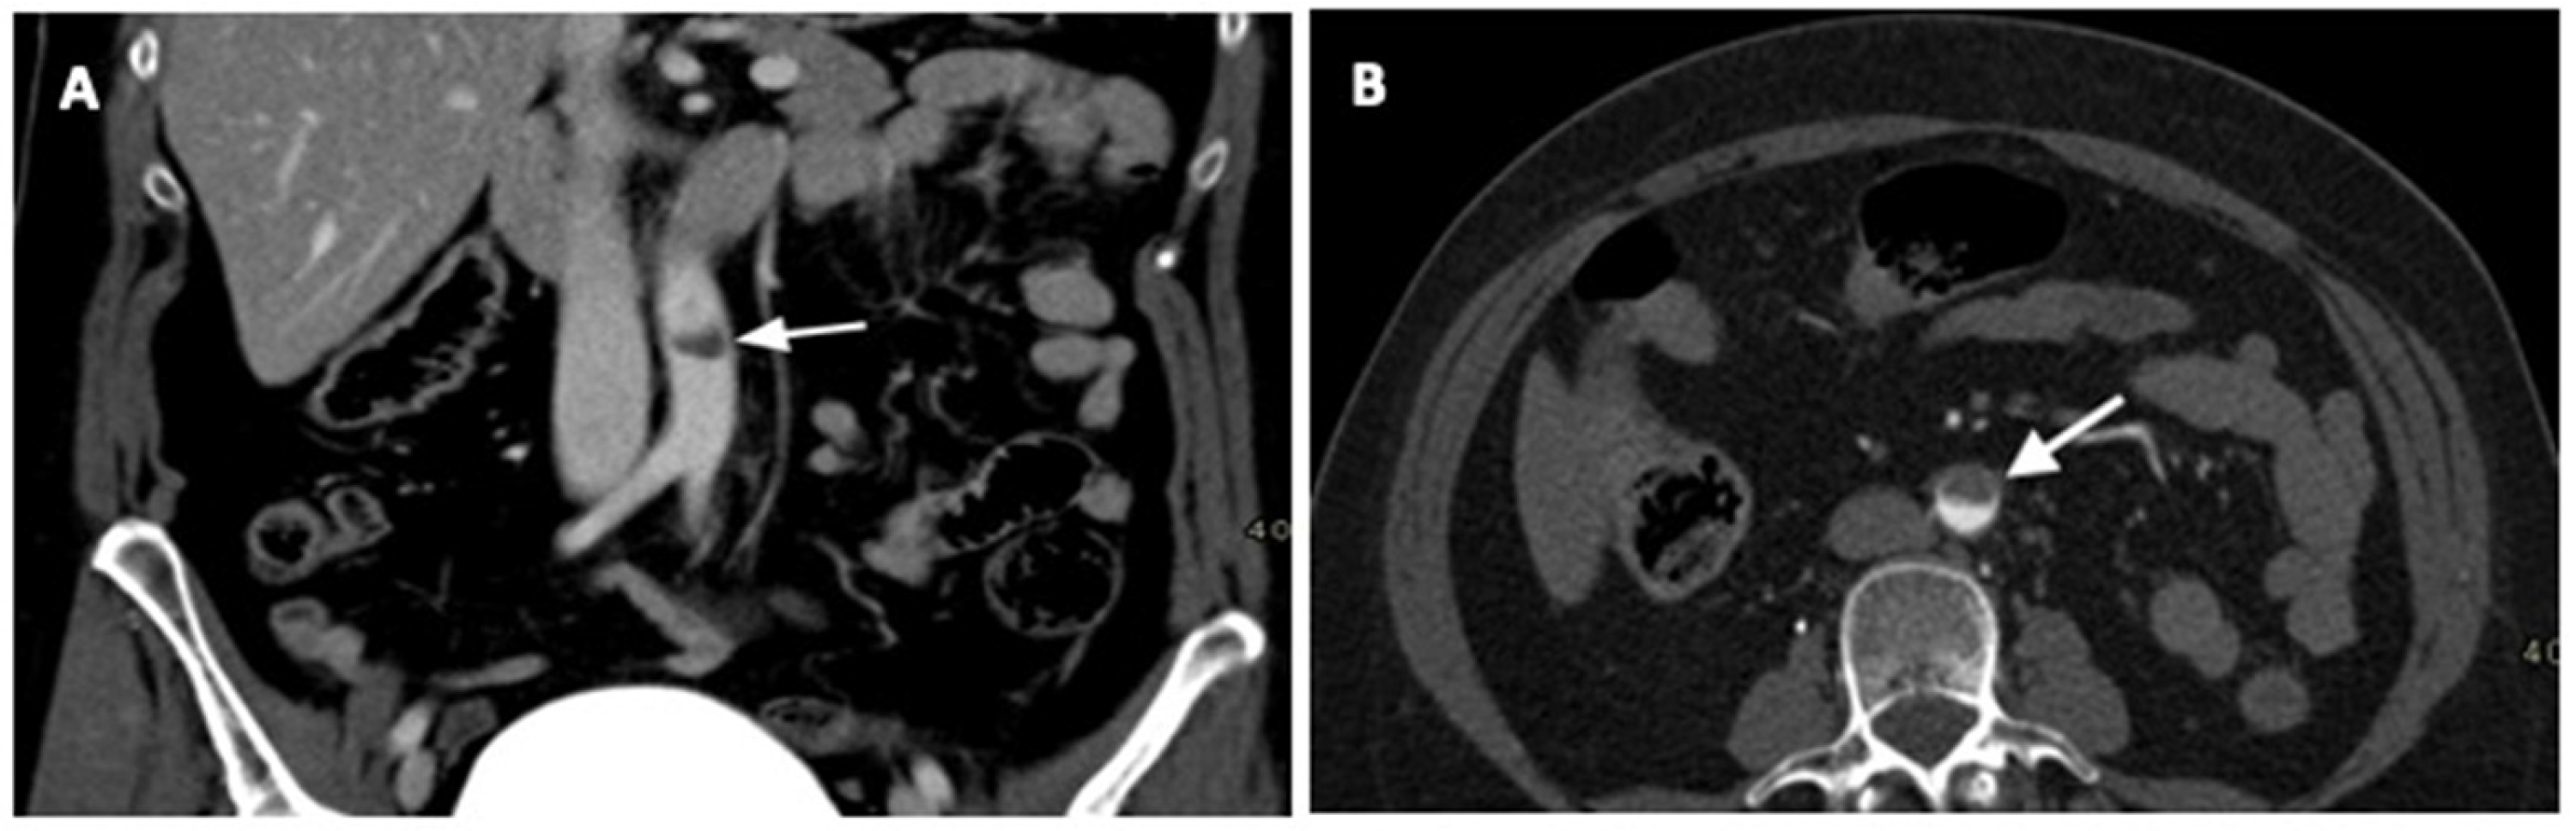

2. Case Report